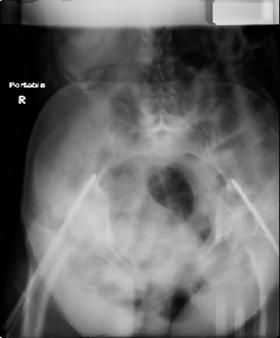

attached are images of a 70 year old female after peds versus car. her own car ran her over.

injuries are limited to the pelvis. left rami open and visible in a 10cm vertical laceration just lateral to left labia majora. wound is grossly clean. no vaginal and no urinary issues. CT scan shows widening of both SI joints anteriorly but I think this is vertically stable pattern.

pt treated that night with I/D and supra-acetabular frame to close the ring. consideration was given for SI screws bilateraly, but given time of night and other factors decision made not to proceed.